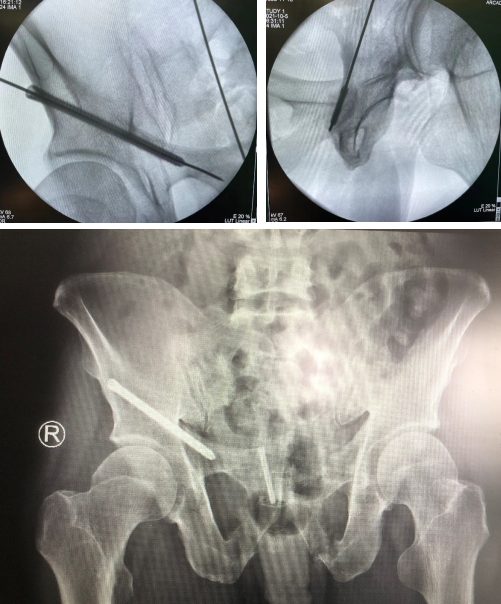

术中,夏建军、郑天龙手术团队通过机器人机械臂的精确运动,以及精准定位,规划螺钉方向及长度,避开髋臼缘及盆腔,拧入100mm空心螺钉后再复位右侧耻骨,准确地将一枚长度38mm空心螺钉置入,透视可见右侧髋臼及右侧耻骨支骨折端间隙明显缩小,顺利完成右髋臼、骨盆骨折闭合复位微创手术——两个手术切口均不到2厘米,令人惊叹。

夏建军副主任医师说,骨科机器人手术中机械臂的精准度超过人手,解决了骨科手术“看不见、打不准、拿不稳”三大难题,让骨科手术更完美。

若是采用传统手术方法,只能进行开放式手术,术中切口达10厘米以上,并且由于缺少可视化设备,要反复地透视定位,且精确性较低,后遗症多,病人康复时间也会因此延长。

而如今,患者手术螺钉精确定位,伤口仅2个“小眼”,不但减少了痛苦,而且通过机器人手术更加精准高效,加速康复,大大缩短术后身体恢复时间。